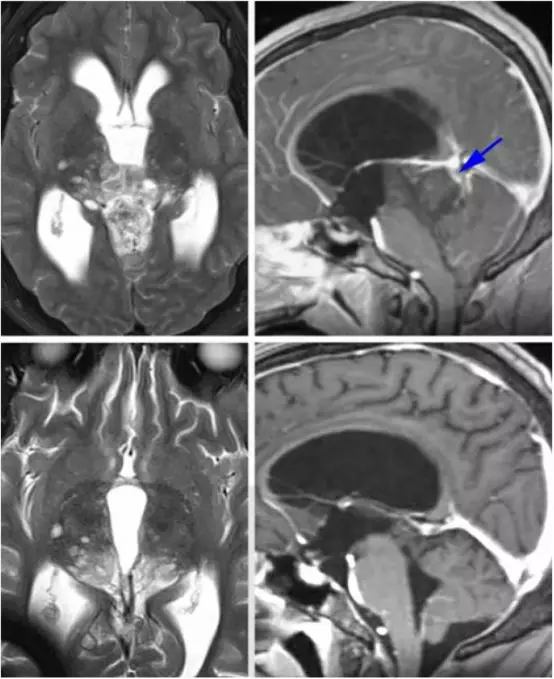

图2. 各种类型的松果体区病变。上排所示为一例松果体囊肿,注意其只有薄层环形强化;下排所示为一例顶盖区毛细胞型星形细胞瘤;而其他病变,如生殖细胞瘤、松果体母细胞瘤和胶质瘤卒中请阅读Selection of Operative Corridor章节。

图4. 对于有些患者,术前仔细评估深部静脉系统是有好处的。如图所示为一例未成熟畸胎瘤患者,术前CT血管成像提示大脑大静脉及其属支位于肿瘤后方(蓝色箭头)。这种静脉结构使得我们不能采用显露更好的小脑上入路,而枕部经天幕入路更为合适。